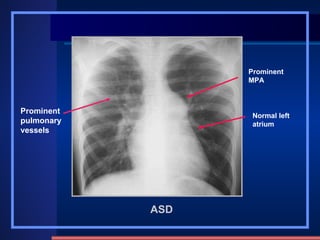

ASD Clinic mostly adult  SM on the 2th-3rd intercostal of the left sternal border Change of hemodynamics X-ray appearance Cardiomegaly , “mitral configuration” RA & RV↑ ,  RA↑ ↑   obviously Pulmonary artery segment bulge  , hilum angiectasia, hilum dance pulmonary blood flow↑ ↑. PAH in later stage LA do not enlarge, LV and aorta shrink /231 4 type: Ostium primum , ostium secundum Sinus venosus , coronary sinus Fossa Ovalis defect 80~90% Atrial septal defect methods normal abnormities diseases

ASD Prominent pulmonary vessels Prominent MPA Normal left atrium

ASD Clinic mostlyadult SM on the 2th-3rd intercostal of the left sternal border Change of hemodynamics X-ray appearance Cardiomegaly , “mitral configuration” RA & RV↑ , RA↑ ↑ obviously Pulmonary artery segment bulge , hilum angiectasia, hilum dance pulmonary blood flow↑ ↑. PAH in later stage LA do not enlarge, LV and aorta shrink /231 4 type: Ostium primum , ostium secundum Sinus venosus , coronary sinus Fossa Ovalis defect 80~90% Atrial septal defect methods normal abnormities diseases

ASD Prominent pulmonaryvessels Prominent MPA Normal left atrium